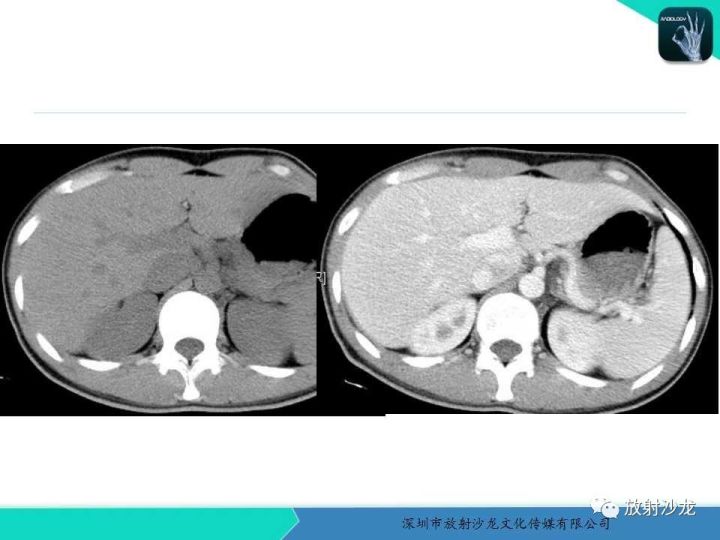

【病例】纵隔卵黄囊瘤1例CT影像表现